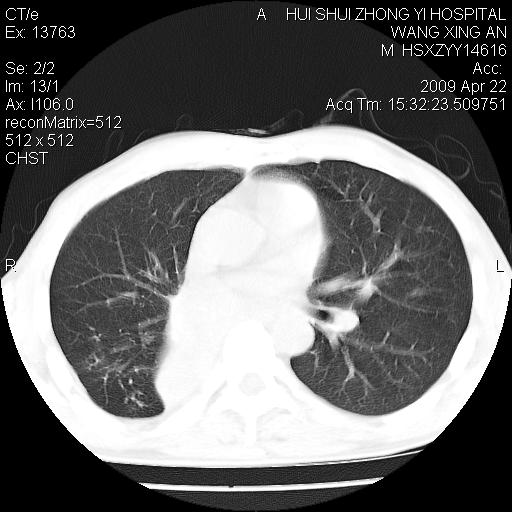

标题: CT19534:患者男、46岁咳嗽、胸痛半月。 [打印本页]

标题: CT19534:患者男、46岁咳嗽、胸痛半月。

1、右下肺中央型肺癌并右肺转移,右肺下叶不张。(肿块围绕右肺下叶支气管生长,致管腔闭塞右肺下叶不张;右肺有结节影)。

2、右侧胸腔积液。

3、右中上肺陈旧性肺结核(右肺见纤维化病灶及点状钙化)。

1)右肺中间段支气管癌并右肺下叶肺不张。2)右肺上叶、两肺下叶背段感染性病变。3)右侧少量胸腔积液。